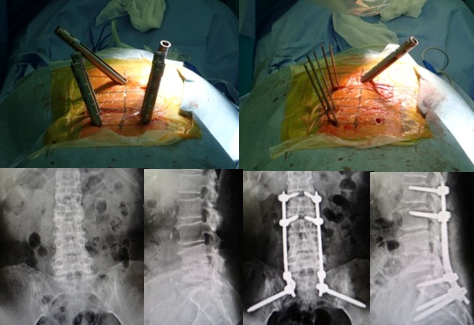

(1)胸椎に肺癌の転移性腫瘍を認めます。脳転移などもあったため、根治的手術は困難でした。

(2)経皮的椎弓根スクリューを用いた特殊な方法で、脊椎を安定化しています。

術後、麻痺の改善と疼痛の緩和を認めました。

腰の第4番目、5 番目の椎体が感染し、進行性の骨破壊と後弯変形を認めます。経皮的椎弓根スクリューを用いた特殊な方法で、脊椎を安定化しています。

(左)術前の進行性の骨破壊が見られましたが、(右)術後1年では良好な骨癒合が得られています。